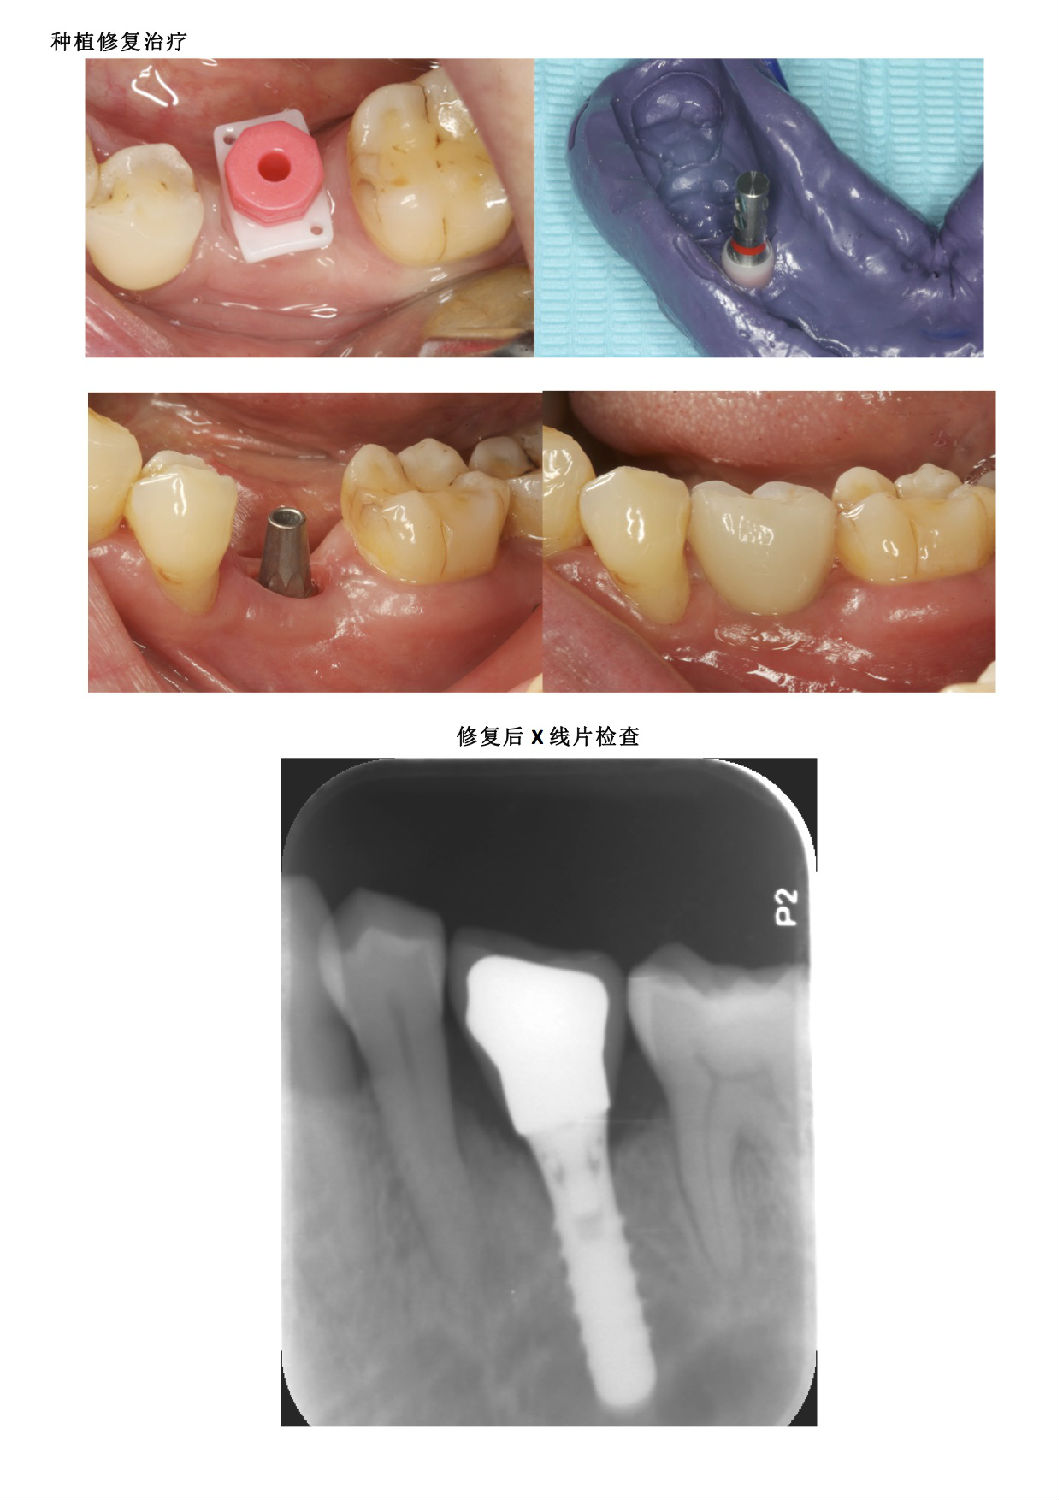

牙周病患者種植治療+鄰牙GTR病例匯報